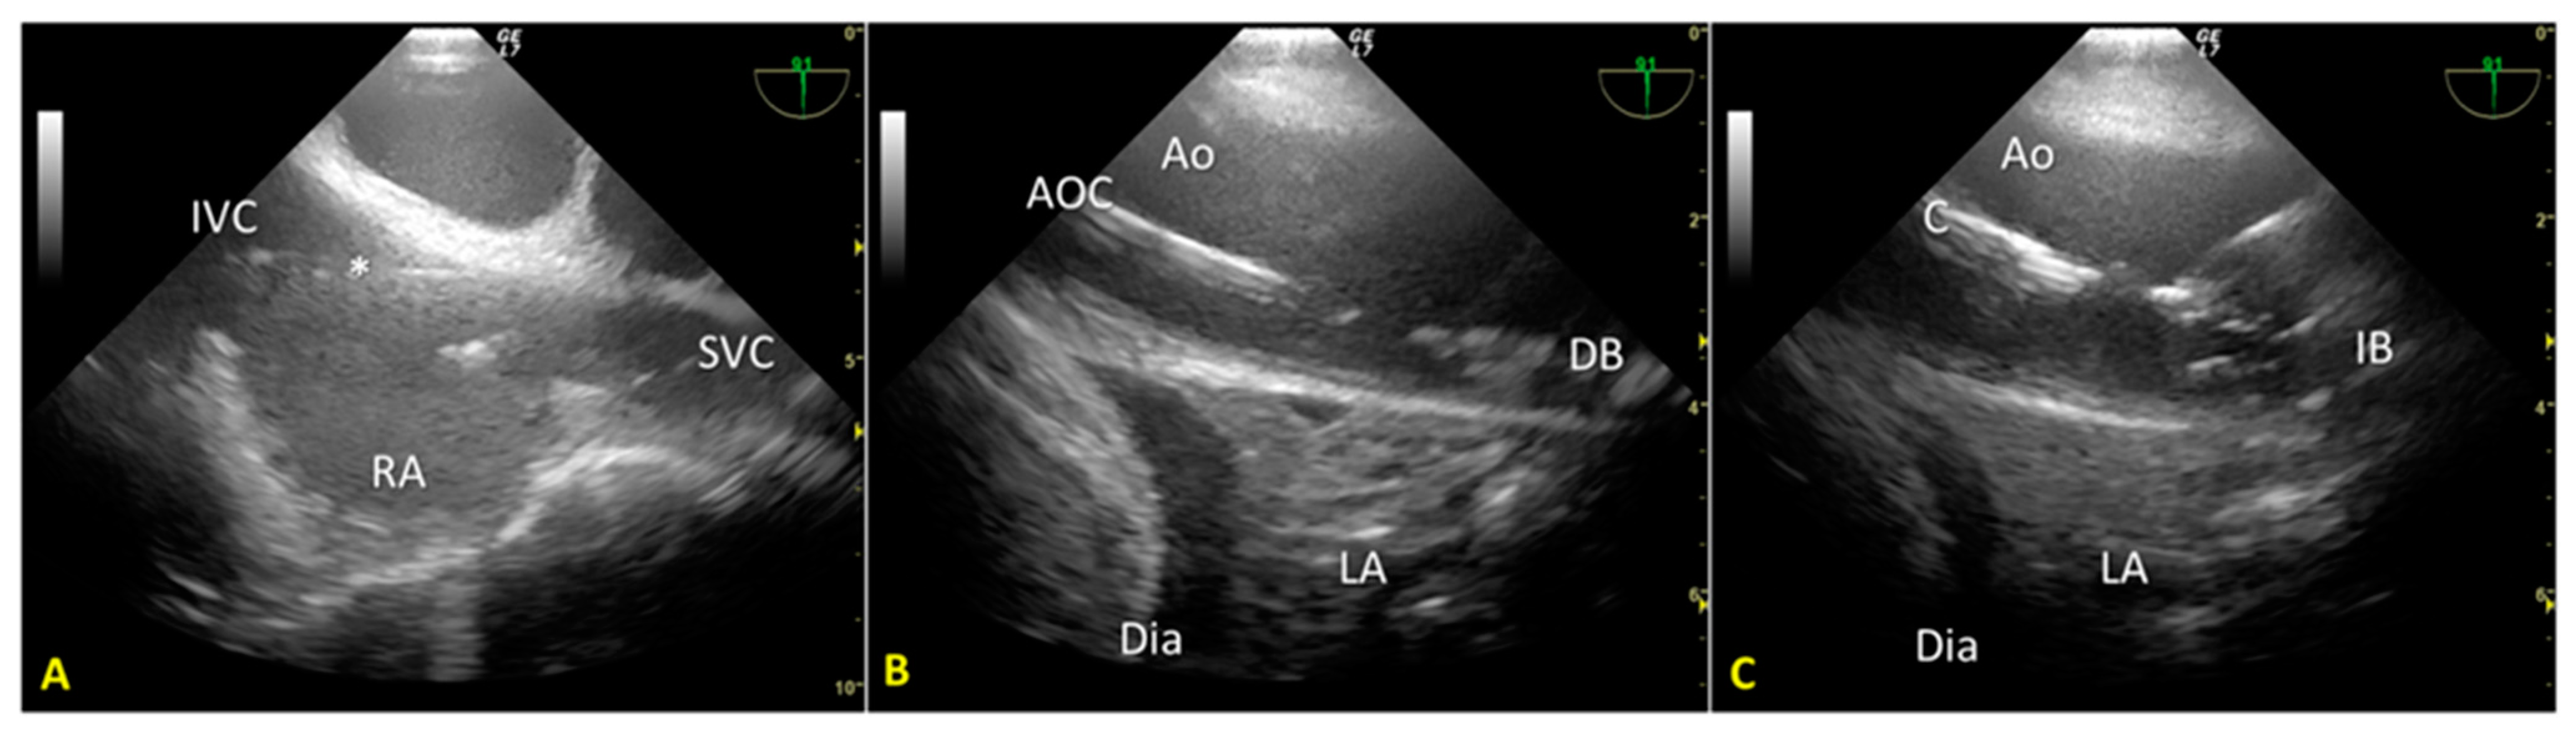

We used an introducer needle to insert a Super Stiff guidewire into the right femoral vein until the right atrium. Correct positioning of the guidewire was verified in real time using the TEE mid-esophageal bicaval view (Figure 1A). Next, we inserted a second guidewire through the right femoral artery sheath and introduced it up to the thoracic aorta. After visualizing the wire’s tip within the thoracic aorta using the mid-esophageal descending aorta short-axis view, we partially withdrew the guidewire so that its tip stopped below the diaphragm. These two guides allowed the introduction of venous and arterial A-NRP cannulae post-mortem.

Finally, we introduced a third guidewire through the left femoral artery sheath to allow proper stent placement for aortic occlusion. TEE use guided and monitored correct positioning using the mid-esophageal descending aorta long-axis view (Figure 1B,C). Using fluoroscopy, we double-checked the proper positioning of the guides and aortic occlusion catheter (AOC).

Figure 1. (A). Mid-esophageal bicaval view. The guidewire (*) was inserted through the inferior vena cava into the right atrium. (B). Mid-esophageal descending aorta long-axis view. The aortic occlusion catheter is visualized in the thoracic aorta; the deflated balloon is located just above the diaphragm. (C). Mid-esophageal descending aorta long-axis view during A-NRP. The position of the AB (inflated) remained unchanged above the diaphragm. IVC—inferior vena cava; RA—right atrium; SVC—superior vena cava; * guidewire; Ao—aorta; AOC—aortic occlusion catheter; LA—lung atelectasis; Dia – diaphragm; DB—desufflated balloon; IB—inflated balloon.